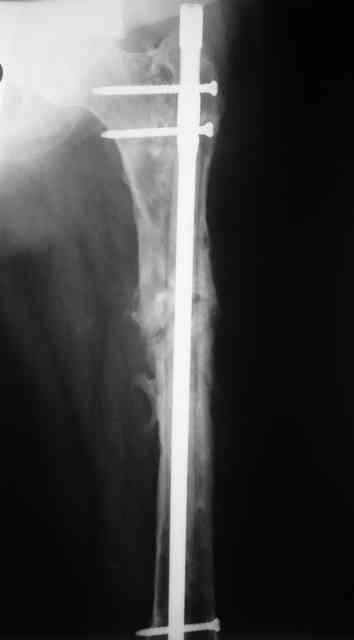

Вчера наш пациент был на контрольном осмотре. Вроде все идет нормально. Рентгенограммы от 25 сентября 2007 г. (прошло 5 месяцев после операции) прилагаю.